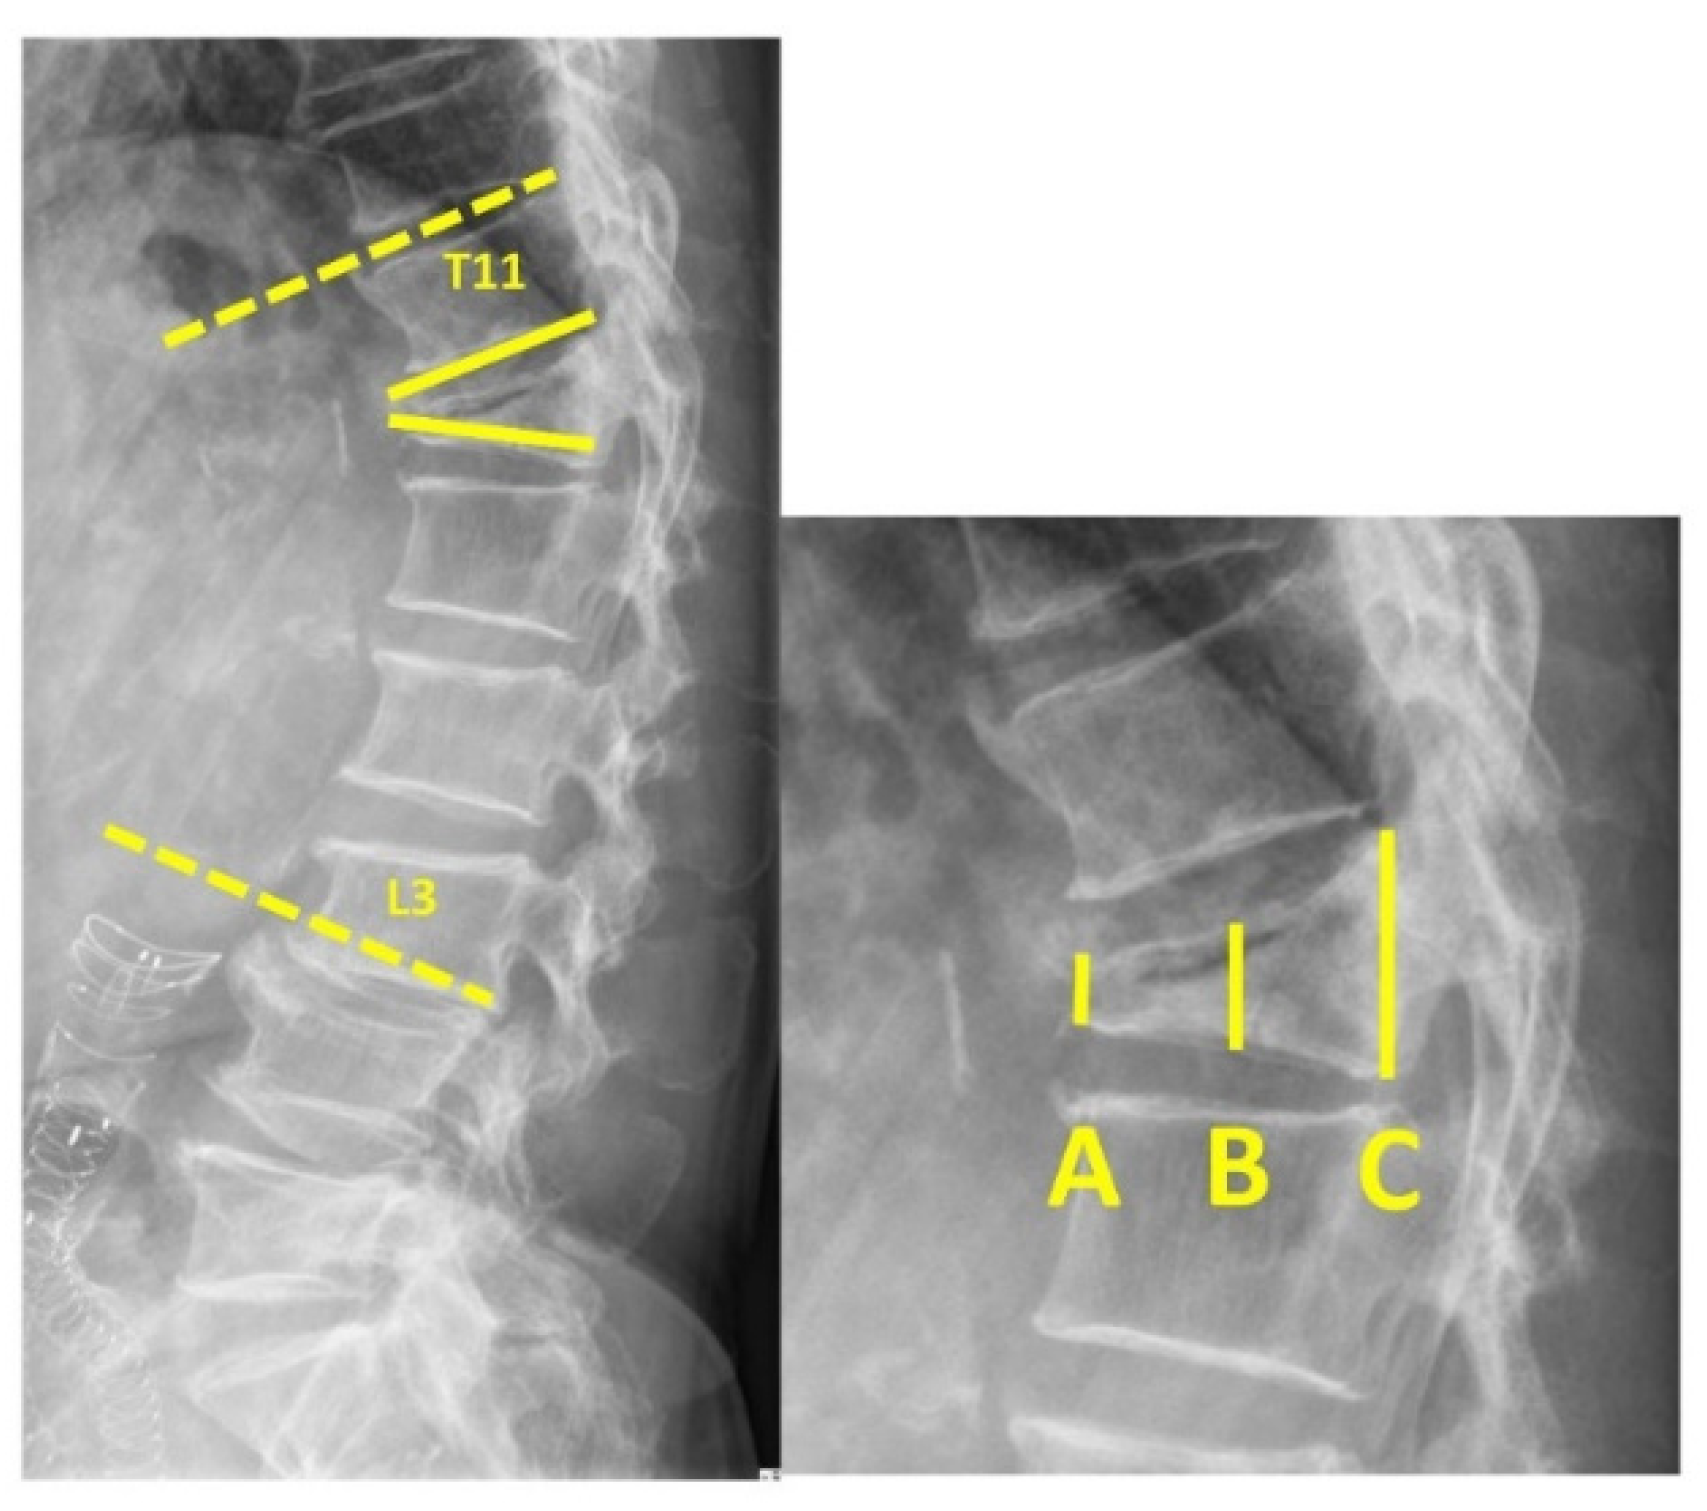

Figure 1. (Left) Regional kyphotic angle—the angle between the upper endplate of T11 and lower endplate of L3 (dashed line). Local kyphotic—the angle between the upper and lower endplates of the fractured vertebra (solid line). (Right) A—anterior VBH, B—middle VBH, C—posterior VBH (VBH = vertebral body height).

All patients underwent a complete preoperative clinical examination that included a detailed medical history and complete radiographic examination to confirm the presence, location, and severity of the VCF. Occasionally, a computed tomography scan was used to assess structural deformities before the procedure. Anterior, middle, and posterior vertebral body heights were recorded directly in the sagittal sections. The regional kyphotic angle was defined as the angle between the upper endplate of T11 and the lower endplate of L3. The local kyphotic angle was defined as the angle between the upper and lower plates of the fractured vertebra.

Image assessment that included anterior, middle, posterior vertebral body heights, and regional and local kyphotic angles was carried out before and after the operation (Figure 1). We defined the “double cross sign” as bone cement that expanded vertically along the bilateral SpineJack system and across the midline of the vertebral body in the anteroposterior (AP) view of the radiographic image (Figure 2). The assessment of the postoperative radiographic image that met the criteria for double cross sign was also conducted and recorded by the same single senior orthopedic spine surgeon (C-CH). In addition, the angle between the two expanded devices was recorded immediately after the surgery, and at the latest postoperative radiographic follow-up (Figure 3).